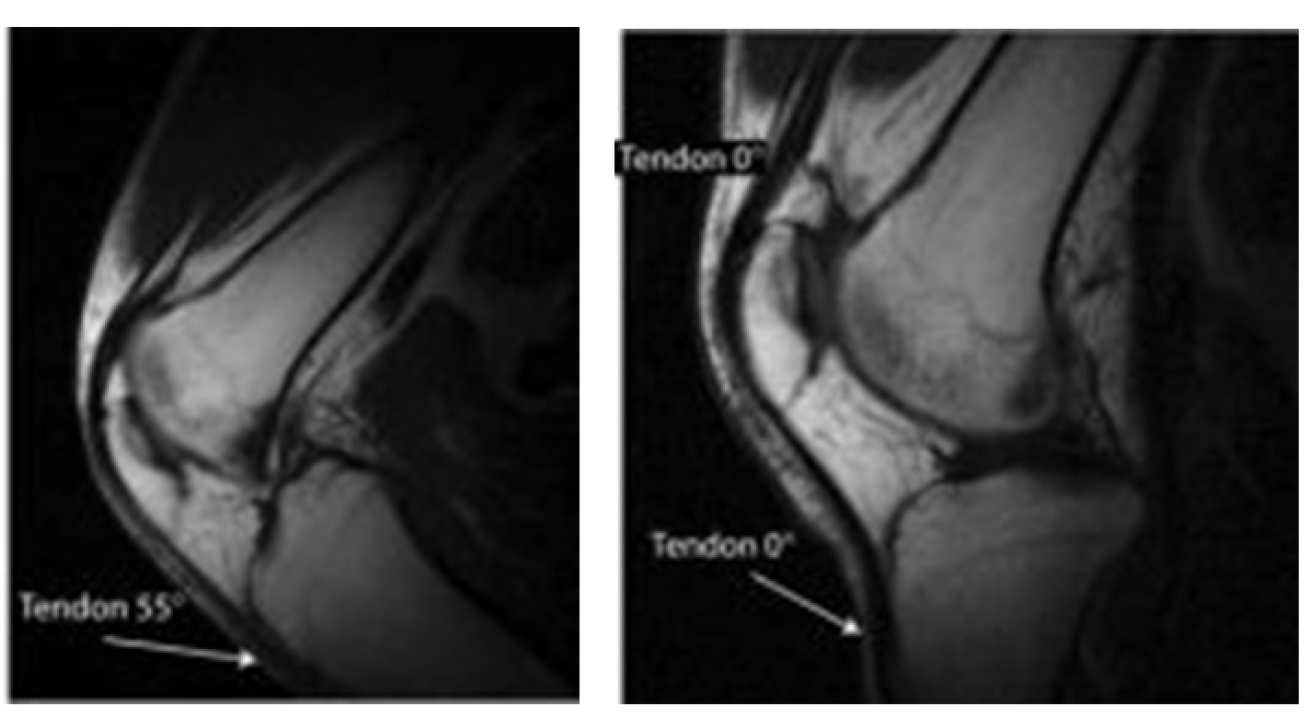

Many significant tissues containing collagen have short relaxation times which make them very hard to image using conventional MRI.

Changing the tissue orientation relative to the direction of the magnetic field can largely resolve this issue, and we have developed a magnet system which permits such changes.

Pairs of anatomical images obtained at different angle of the main field, arrows are used to mark tissues experiencing signal changes due to the magic angle effect.